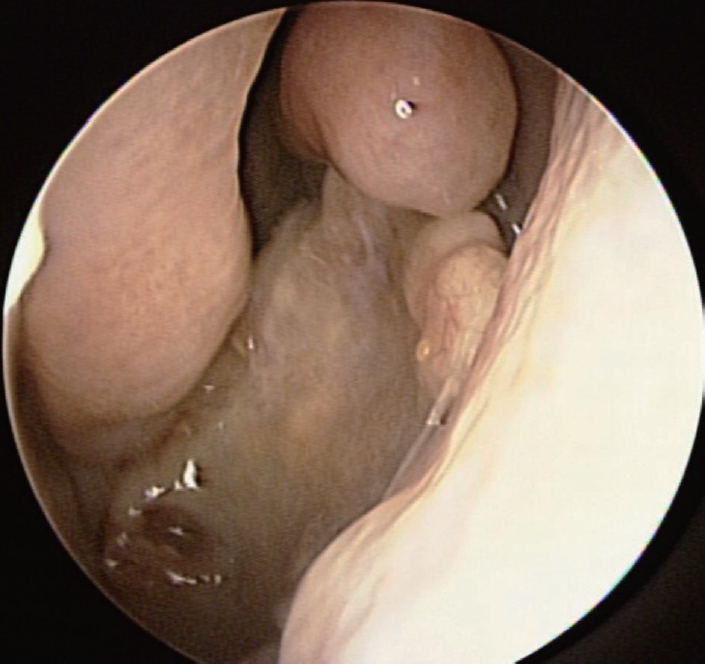

증 례이전 안면 외상, 수술력 포함하여 특이병력 없이 건강하였던 41세 여자 환자가 15년 전부터 서서히 악화되는 좌측 안와 주위통, 안구돌출을 주소로 내원하였다. 어지럼증, 사지 위약감, 실조 등의 신경학적 증상은 부인하였고 이외 다른 비증상, 안증상도 부인하였다. 비내시경 검진상 우측 비중격 만곡증 및 좌측 비강의 중비도에 정상점막으로 덮힌 팽창성 돌출 병변이 관찰되었다(Fig. 1).

이에 점액낭종을 동반한 좌측 사골동 섬유 이형성증으로 진단하였고, 임상증상이 병변의 위치와 상관 관계가 일치하고 점액낭종이 동반되어 있기에 부비동 내시경을 이용한 수술을 계획하여 시행하였다. 전신마취하 내시경 검진 후 좌측 섬유이형성증 감량술, 점액낭종 조대술 및 좌측 중비도 상악동개방술(middle meatal antrostomy)을 시행하였다. 특징적인 소견으로 프리어 엘리베이터(freer elevator), 절단 겸자(cutting forceps)로 병변의 전방 격막을 제거하자 한차례 점액낭종이 조대되었고 이어 미세절삭기(debrider)로 후상방에 위치한 두 번째 점액낭종의 조대술을 시행하였다. 그 내부에는 갈색의 점액성 분비물이 가득 차 있었다(Fig. 3).

NotesAuthor Contribution Conceptualization: Seung Heon Kang, Hyun Jik Kim. Data curation: Seung Heon Kang, Hyunkyung Cha, Seung Cheol Han. Formal analysis: Seung Heon Kang, Hyun Jik Kim. Funding acquisition: Seung Heon Kang. Investigation: Seung Heon Kang. Methodology: Seung Heon Kang. Project administration: Seung Heon Kang. Resources: Seung Heon Kang. Supervision: Hyun Jik Kim. Validation: Seung Heon Kang. Visualization: Seung Heon Kang. Writing—original draft: Seung Heon Kang. Writing—review & editing: Seung Heon Kang. Fig. 1.Endoscopic finding of expansile extruding mass covered with normal mucosa in left middle meatus. Fig. 2.Left ethmoid fibrous dysplasia combined with mucocele (A) eroded lamina papyracea (B) involvement of pterygoid plates (C) hypoplastic left maxillary sinus and right septal deviation. Fig. 3.Endoscopic findings of operation (A) brownish content spilled out from the mucocele (B) visualization of septated mucoceles (asterisks) after removal of anterior wall of fibrous dysplasia (C) after marsupialization. Fig. 4.Histopathologic findings of FD, pathologic report of FD: osteoid trabeculae that are narrow, curvilinear or irregularly-shaped are arranged haphazardly in a background of dense fibroblastic stroma (hematoxylin and eosin, original magnification ×20). FD: fibrous dysplasia. REFERENCES1. Weinstein LS, Shenker A, Gejman PV, Merino MJ, Friedman E, Spiegel AM. Activating mutations of the stimulatory G protein in the McCune-Albright syndrome. N Engl J Med 1991;325(24):1688-95.